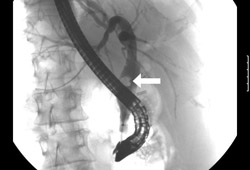

- colangiopancreatografia retrógrada endoscópica (CPRE)

- colangiografia trans-hepática percutânea (CTP)